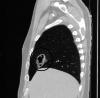

The Streptococcus anginosus group (SAG) consists of three bacteria (Streptococcus intermedius, Streptococcus constellatus, and Streptococcus anginosus) that are known commensals of the upper respiratory, digestive, and reproductive tracts. While a rare occurrence, these bacteria have the capability of causing devastating pyogenic infections and ensuing abscess formations. It is often difficult to distinguish this group as a contaminant or the offending organism (as it is often cultured in respiratory specimens); therefore, it is important to understand the risk factors, clinical presentation, and diagnostic findings that can provide a more accurate picture to identify the organism. Published literature pertaining to the SAG group has rarely documented any invasive surgical intervention that was undertaken for treatment. We describe a case of a 59-year-old male who presented for persistent chest pain and profuse productive cough weeks after he was diagnosed with a left lower extremity deep vein thrombosis and right-sided pulmonary embolism. The patient was found to have a rapidly evolving Streptococcus constellatus right middle lobe lung abscess complicated by a right hemithorax empyema. Management included an exploration of the right chest, decortication, parietal pleurectomy, and partial excision of the right middle lobe. Subsequently, the patient completed four weeks of antibiotics with ertapenem.